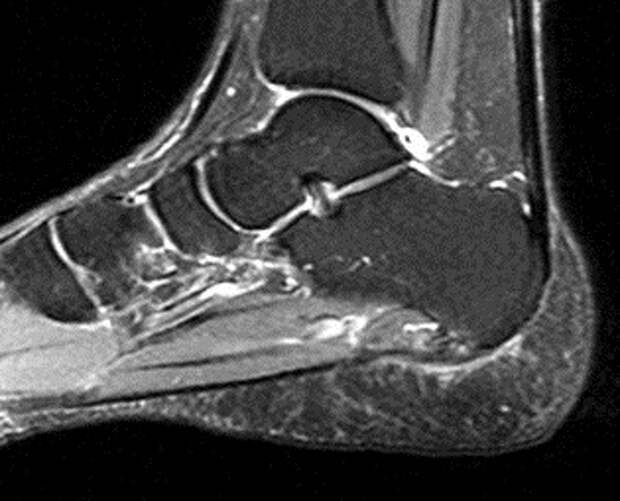

Пример снимка: На МРТ здоровой стопы плантарная фасция выглядит как тонкая (2-3 мм) темная полоска. При фасциите она будет утолщена (5 мм и более) и будет иметь "светящийся" сигнал из-за отека.

На МР-изображениях будут видны следующие характерные признаки:

- Утолщение плантарной фасции у места ее прикрепления к пяточной кости (это ключевой признак).

- Отек (скопление жидкости) внутри и вокруг фасции, что выглядит как яркий сигнал на T2-взвешенных и STIR-изображениях.

- Костный отек в прилежащей части пяточной кости.

- Признаки частичного разрыва: discontinuity волокон фасции, гематома.